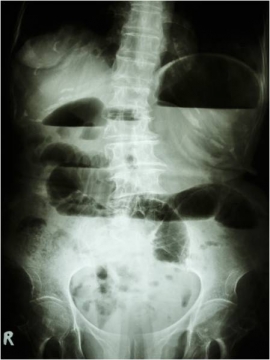

Ορισμοί- Ταξινόμηση- Αιτιολογία Ειλεός αποκαλείται η παρεμπόδιση της φυσιολογικής προώθησης του περιεχομένου του εντέρου, με αποτέλεσμα μία κλινική συνδρομή που περιλαμβάνει κοιλιακό άλγος, μετεωρισμό, ναυτία με εμέτους και αναστολή της αποβολής αερίων και κοπράνων. Το συνηθέστερο αίτιο του ειλεού είναι η απόφραξη του λεπτού εντέρου η οποία αποτελεί και την…